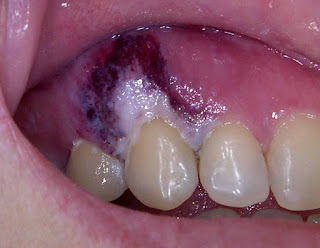

Durante o tratamento oncológico, porém, o virus pode se manifestar um pouco diferente, provocando feridas dentro da boca - em cima da língua, no palato (céu da boca), na gengiva e bordos de língua. São lesões muito dolorosas, com aspecto profundo, mesmo que não sejam muito extensas. É preciso sempre fazer um diagnóstico correto, pois quando temos infecção por herpes durante o tratamento oncológico precisamos entrar com medicação sistêmica, ou seja, não adianta

só passar pomadinha, precisa tomar remédio mesmo. A laserterapia ajuda a aliviar os sintomas e cicatrizar mais rápido as lesões, mas é preciso medicar para controlar o vírus (sempre pensando em não deixar as infecções da boca irem para o resto do organismo). Essas são fotos de lesões de herpes no palato e gengiva, no mesmo paciente.